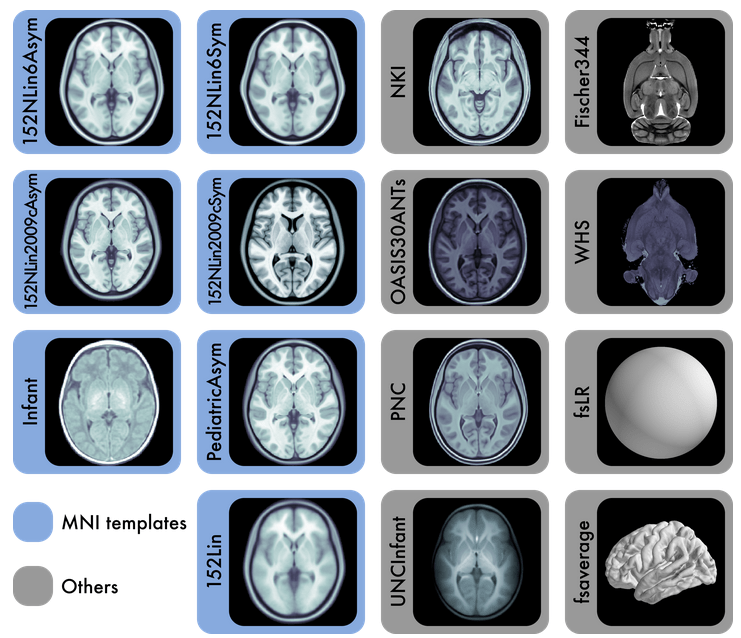

Specify the output spaces you want.

any template from TemplateFlow

(default MNI152NLin2009cAsym)

[they have kid templates too]

or non-standard spaces